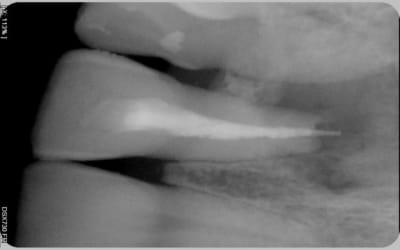

Voici les photos.

Comme vous pouvez le voir la lésion est très importante. Pensez-vous que cette dent ai une chance? Mon maître de stage lui laissait 40% de chance, je n'ai pas de recul mais ça me semble beaucoup. J'ai preferé dire au patient que ça serrait délicat car il n'imaginait même pas la possibilité d'enlever la dent.

Pour la résection apicale, j'y avais penser mais la racine me semble déjà bien courte.

C ne en place ug4pvg - Eugenol

Obturation ocz3kw - Eugenol

je précise qu'en vestibulaire, il y a une voussure, c'est dépressible ce qui me premet de penser à la perte de la table osseuse externe

Si je puis me permettre, pour le problème du dépassement, il faut que tu revois l'étape "ajustage du maître cône" pour faire tes endos.

Car je dirais, sur la radio d'essayage du cône, qu'il est ok en longueur, mais certainement pas en diamètre. Du coup, je pense qu'il frottait assez haut dans le canal et pas au niveau apical. Lorsque tu as condensé (j'imagine avec un spreader.), le cône a glissé à travers l'orifice apical.

Mon cône est de calibre 30, c'est le plus gros que j'avais.

D'accord avec Hinanui en ce qui concerne le maître cône et la nécessité d'une restistance au retrait, surtout quand l'apex paraît élargi comme c'est le cas sur ta radio.